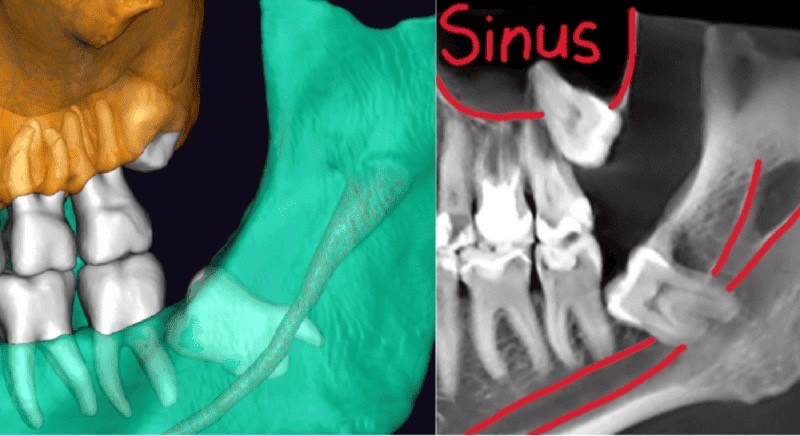

Kompyuter tomografiyasi va 3D rekonstruksiya natijalarida pastki aql tishi sohasida pastki jag‘ nervi ildizlarga juda yaqin joylashgani, yuqori tomonda esa tish yuqori jag‘ bo‘shlig‘i (gaymor bo‘shlig‘i) bilan chegaradosh ekanligi aniqlandi.

Bunday anatomik sharoitda olib tashlashning murakkabligi shundaki, pastki jag‘da operatsiyadan keyin lab va iyak terisining sezuvchanligi pasayishi mumkin, yuqorida esa gaymor bo‘shlig‘i bilan aloqa hosil bo‘lish xavfi mavjud.